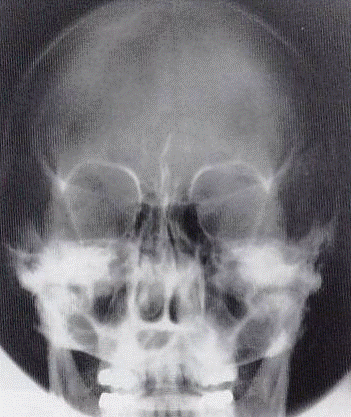

Patología Demostrada

Fracturas y alteraciones de los huesos faciales:

Estructuras Anatómicas Visibles

Órbitas simétricas, senos frontales nítidos, sin rotación.

Evaluar relación dientes-senos maxilares.

Caldwell vs Waters

CALDWELL

Angulación: 15° caudal

Punto salida: Nasión

Mejor visualiza: Senos frontales, órbitas